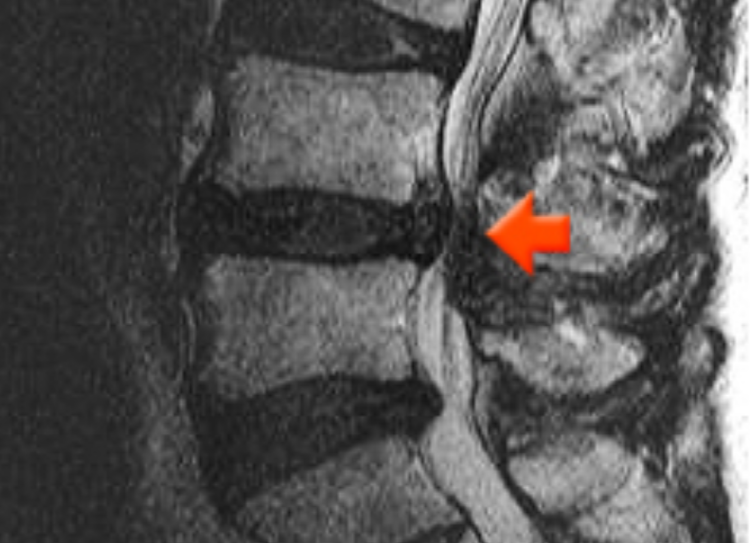

허리디스크 내부 손상이 일어나서 생긴 미세한 찢어짐은 MRI 촬영에서도 구분하기가 힘드니 허리디스크가 터지고 난 뒤에나 MRI로 확인할 수가 있습니다. 그래서 허리디스크 환자가 되지 않으려면 허리 삐끗했을때 무엇보다 바른 자세 관리가 중요합니다.